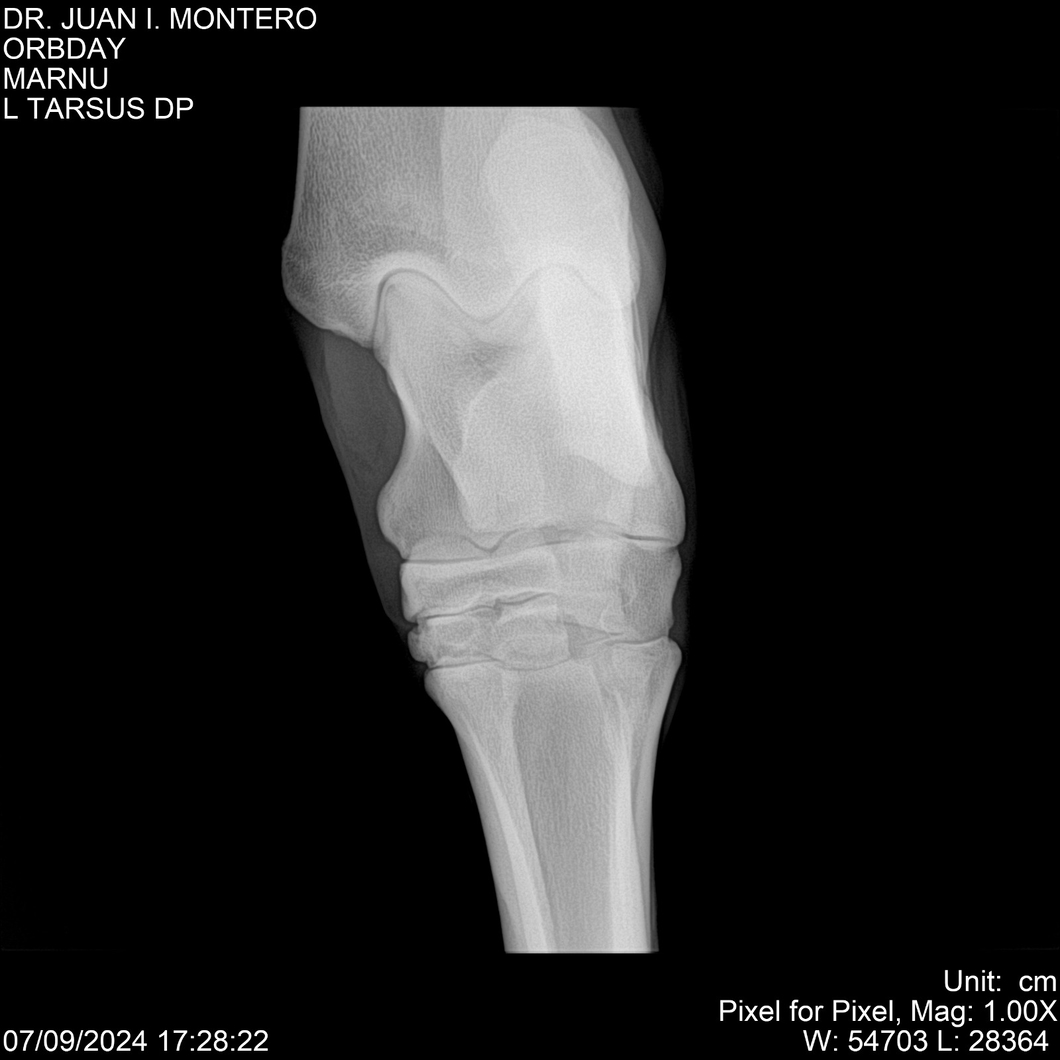

• Empresa: Abelenda N. R., Walter Hugo